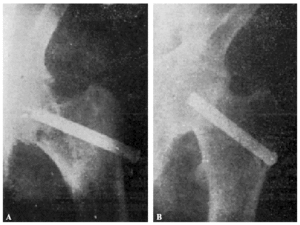

Fracaso número 2(observación número 2). F. S., setenta años4. Ingresa en el servicio con una fractura mediana del cuello femoral izquierdo. Osteosíntesis extraarticular (fig. 3. A y B). La impactación no ha resultado perfecta.

Figura 3. A: obs. núm. 2. El clavo no penetra suficientemente y la impactación, salvo en la parte superior de la línea de fractura, es muy defectuosa. B: obs. núm. 2. La posición del clavo es buena. C: obs. núm. 2. El clavo tiende a ser expulsado hacia fuera y apenas penetra en la cabeza femoral.

A los veinte días de la intervención pasa el enfermo a su domicilio, recomendándole que continúe en la cama. Pasado un mes vemos nuevamente al enfermo, el cual nos manifiesta que anda con mucha más dificultad que en los primeros días de permanecer en su domicilio, que fue cuando, por no haber interpretado bien nuestras indicaciones, comenzó a emprender la marcha. La radiografía (fig. 3. C) demuestra que el clavo apenas penetra en la cabeza femoral. A los ocho días hacemos otra radiografía (fig. 4. A), observándose que el trocáncer ha ascendido, a pesar de continuar guardando cama el enfermo. Ingresa nuevamente en el servicio, donde, con anestesia raquídea, retiramos el clavo, reduciendo las fracturas y volviendo a colocar un clavo más largo en buena dirección (fig. 4. B). Una radiografía practicada siete años y medio más tarde demuestra la no consolidación de la fractura, trastornos tróficos en cuello y cabeza femoral y que el cabo ha penetrado en el fondo de la cavidad cotiloidea, en donde ha labrado una cavidad (fig. 4. C).

Figura 4. A: obs. núm. 2. El trocánter ha ascendido francamente con relación a la radiografía anterior. El clavo tiende a salir de la cabeza por su parte superior. B: obs. núm. 2. Se extrajo el clavo y se colocó otro. El nuevo clavo está colocado en buena dirección, pero la reducción no es perfecta. C: obs. núm. 2. El clavo ha penetrado en el fondo de la cavidad cotiloidea, en cuyo lugar ha labrado una cavidad. Trastornos tróficos en cuello ycabeza femoral. El cuello del fémur ha desaparecido casi completamente.

En este caso el fracaso se debe a que la impactación no fue perfecta, y sobre todo, a haber el enfermo iniciado la deambulación al mes de intervenido, a pesar de que nosotros le ordenamos que guardara cama.